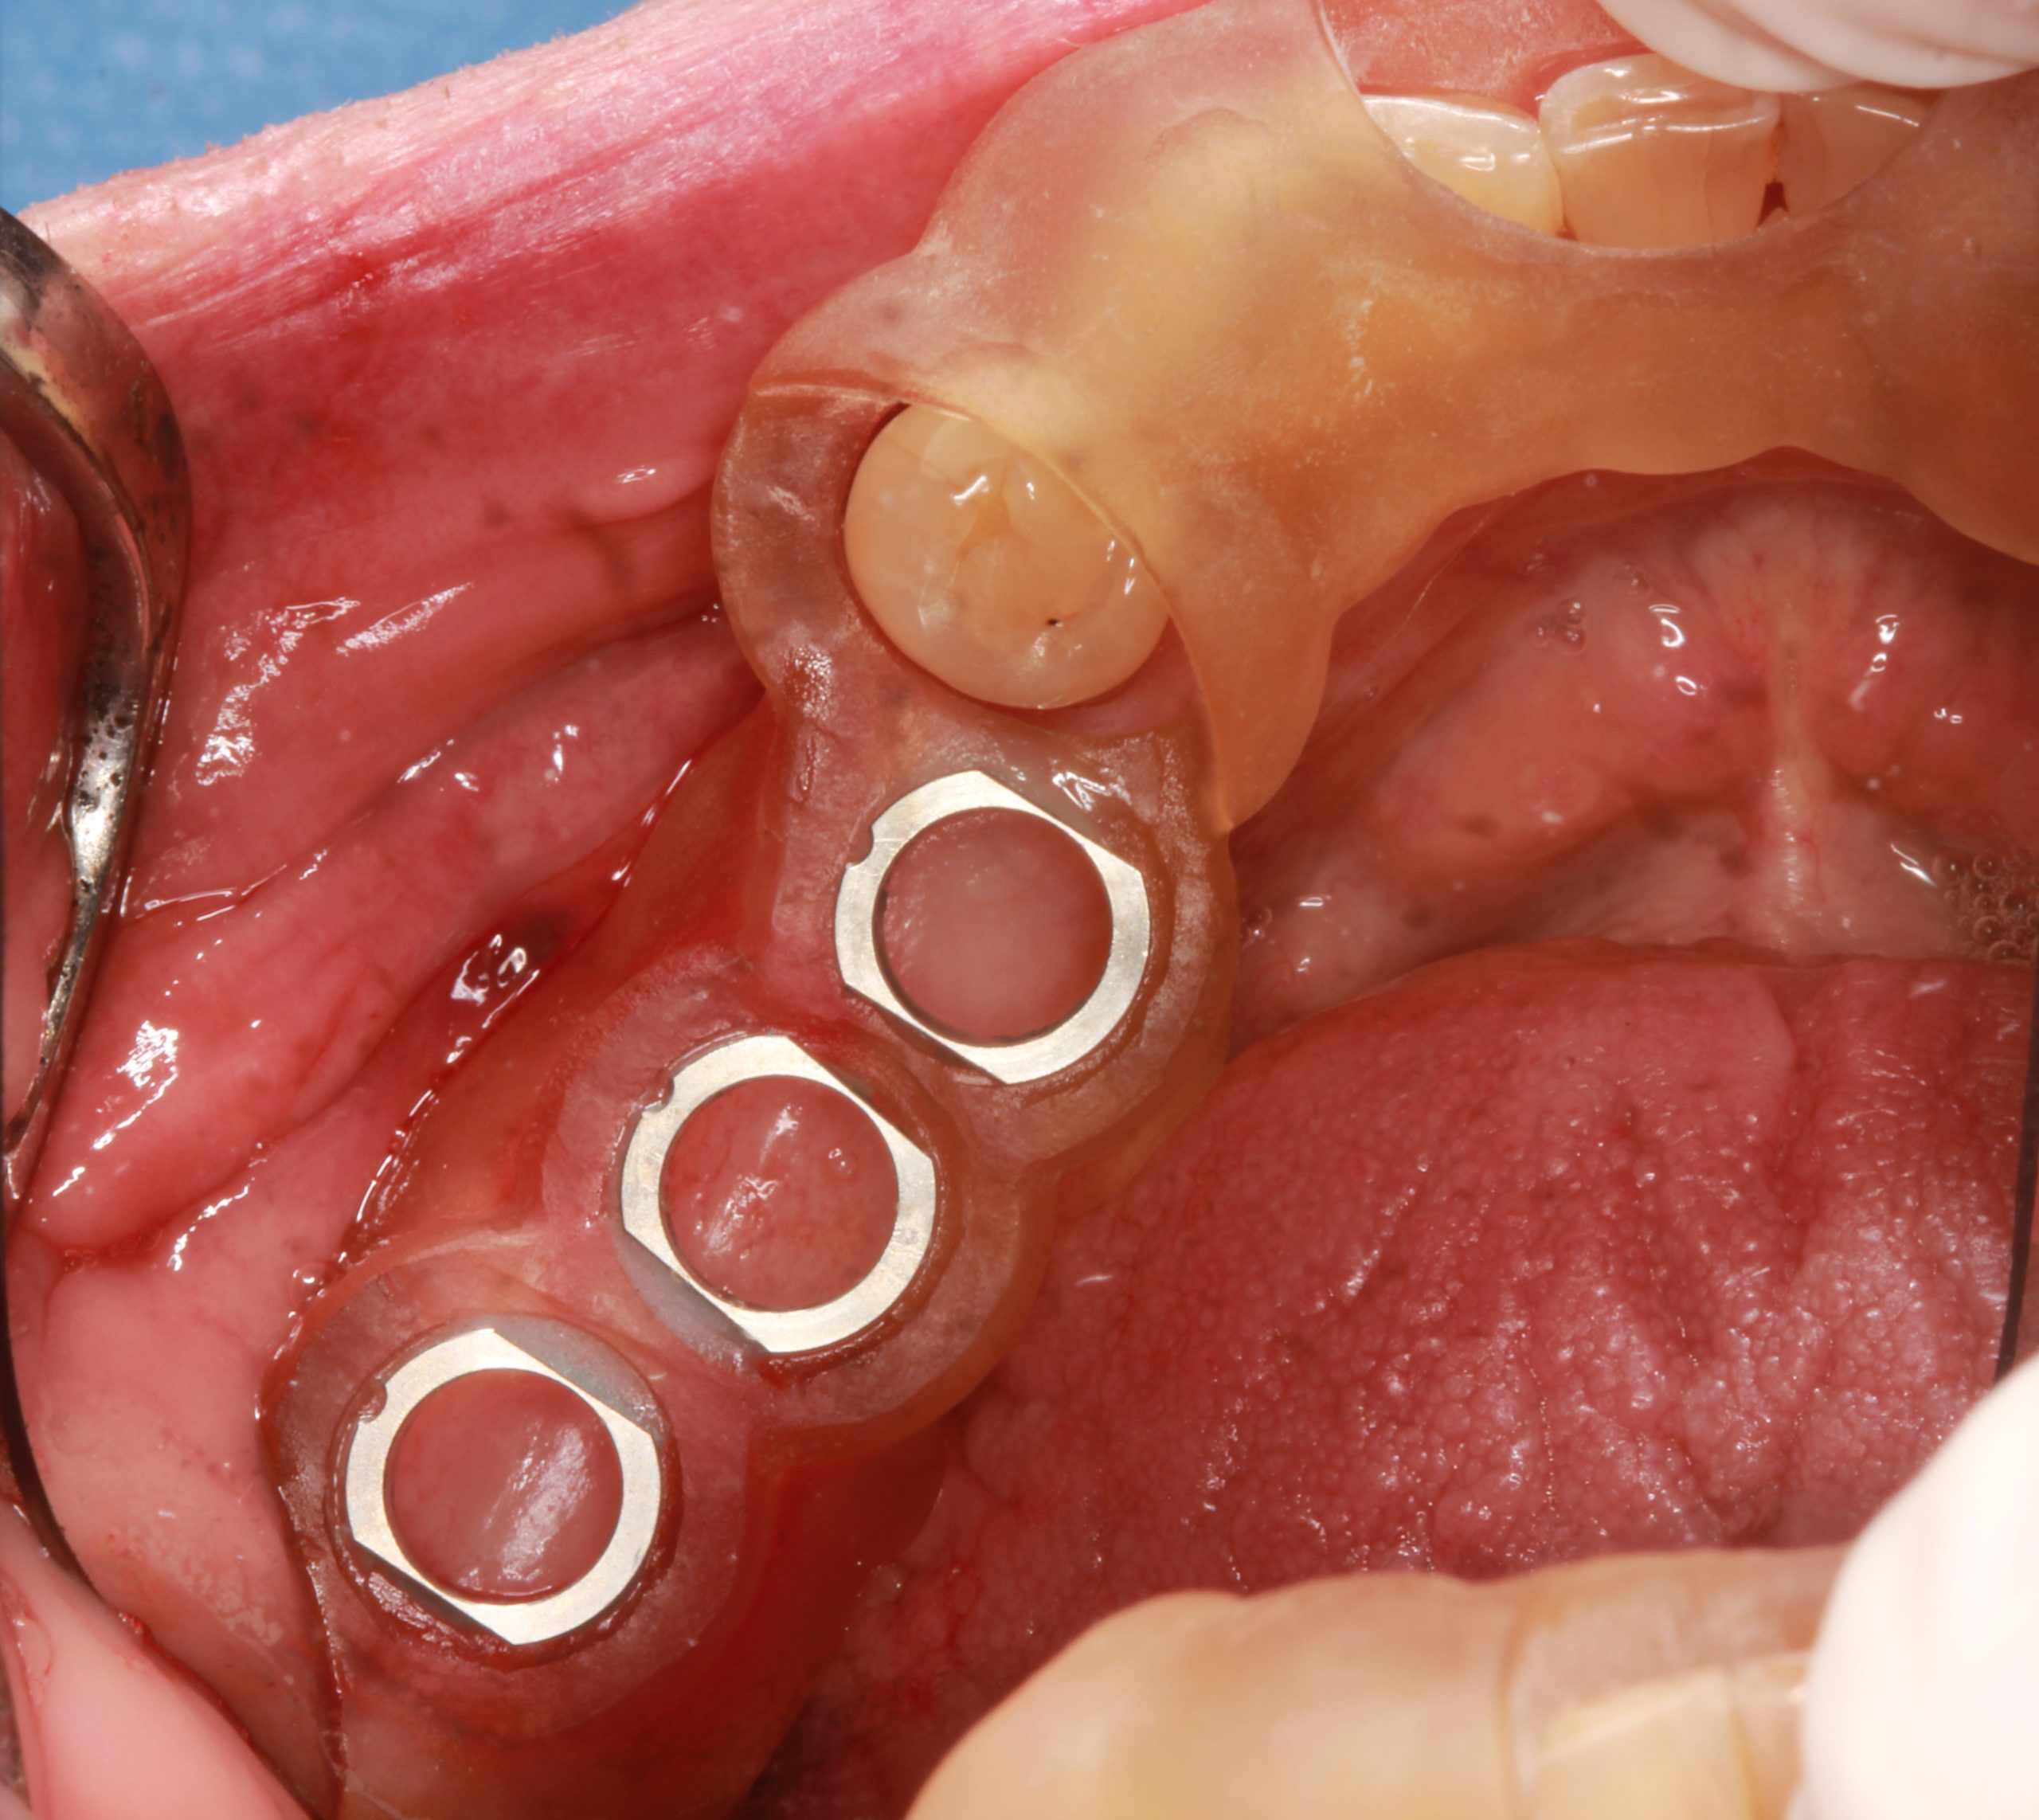

After rehearsing the exact fitting of the tooth-supported surgical template in the mouth, the implants were placed in the planned positions.

In accordance with the surgical protocol, the S2.9 guided drill with the required length and an S2.9 drill guide (with the same color strip) of the smallest diameter of 2.3 mm were used.

Then the treatment was continued with the drills and the drill guides for the appropriate implant diameter.

The preparation was completed using guided countersinks and threadformers with C-guides. After the surgical template was removed, the implant was placed.